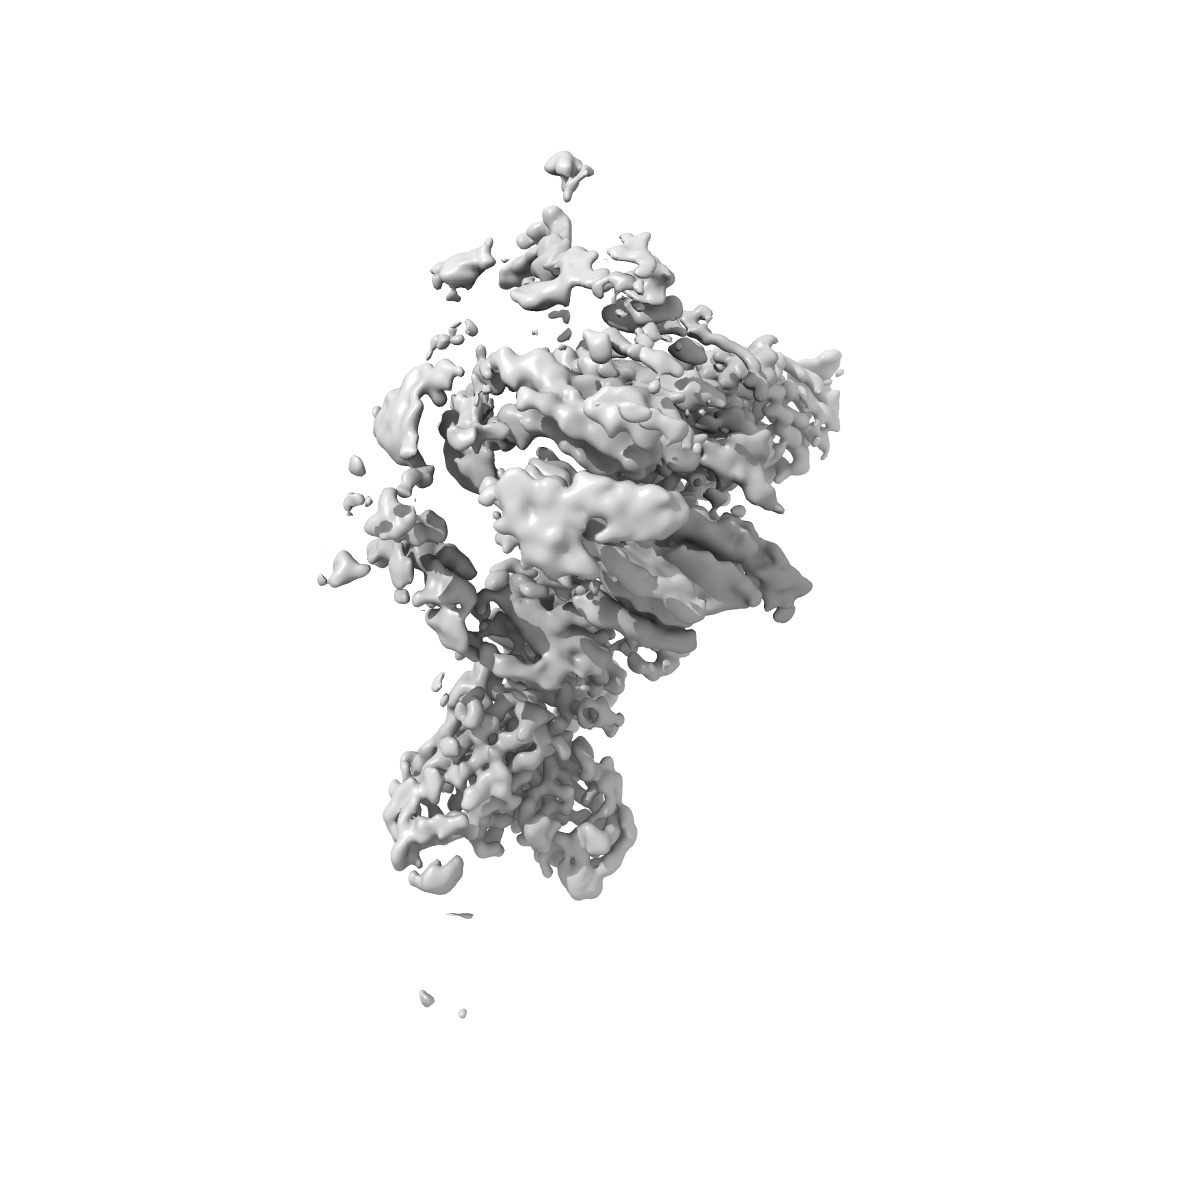

Cryo-EM structure of S309-RBD-RBD-S309 in the S309-bound Omicron spike protein (local refinement)

Single-particle2.66 Å

Sample: Cryo-EM structure of the Omicron RBD-RBD-S309 complex from the S309-bound Omicron spike protein (local refinement)

Omicron SARS-CoV-2 mutations stabilize spike up-RBD conformation and lead to a non-RBM-binding monoclonal antibody escape.

(2022) Nat Commun , 13 , 4958 - 4958